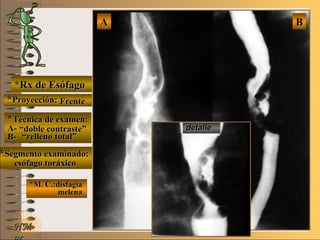

*Rx de Esófago*Rx de Esófago

**Proyección:Proyección:

**Técnica de examen:Técnica de examen:

A-A-

B-B-

**Segmento examinado:Segmento examinado:

*M. C.:disfagia*M. C.:disfagia

melenamelena

NMNM

FrenteFrente

““doble contraste”doble contraste”

““relleno total”relleno total”

esófago toráxicoesófago toráxico

A-A-El examen es normal o patológico?El examen es normal o patológico?

Examen patológico de esófago toráxico con téc-Examen patológico de esófago toráxico con téc-

nica A- doble contraste y B- relleno total en pro-nica A- doble contraste y B- relleno total en pro-

yección de frenteyección de frente

B-B-La patología es congénita o adquirida?La patología es congénita o adquirida?

Patología adquiridaPatología adquirida

D-D-La misma es neoplásica o no neoplásica?La misma es neoplásica o no neoplásica?

Patología adquirida orgánica neoplásicaPatología adquirida orgánica neoplásica

E-E-Puede describir la o las imágenes patológicas?Puede describir la o las imágenes patológicas?

Se identifica en el borde izquierdo de tercio medioSe identifica en el borde izquierdo de tercio medio

de esófago toráxico una imagen elevado-depri-de esófago toráxico una imagen elevado-depri-

mida, de bordes irregulares, relleno heterogé-mida, de bordes irregulares, relleno heterogé-

neo, compatible con C.A. avanzado tipo II deneo, compatible con C.A. avanzado tipo II de

BorrmannBorrmann UNTUNT

C-C-Dicha patología es orgánica, funcional o mixta?Dicha patología es orgánica, funcional o mixta?

Patología adquirida orgánicaPatología adquirida orgánica